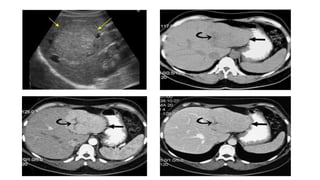

Hemangioma

A, Hemangioma. Ultrasonography demonstrates

a large circumscribed uniformly hyperechoic

mass in the right hepatic lobe

B, Ultrasonography demonstrates atypical hypoechoic

appearance of a large hemangioma (in the setting of an

echogenic liver due to hepatic steatosis).